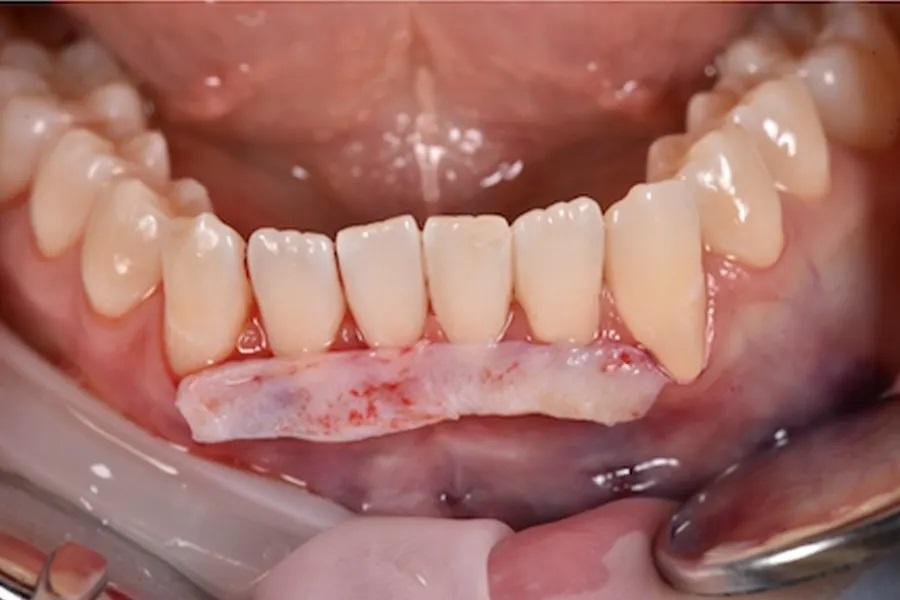

Пародонтологическое лечение при тонком фенотипе

При тонком фенотипе с начальными рецессиями минимально инвазивная тоннельная техника с применением СТТ (при необходимости — с использованием эмалевых матриксных белков на оголенных корнях) позволяет увеличить толщину мягких тканей и обеспечить долгосрочную стабильность после ортодонтического перемещения зубов. (фото 13 – 16)

Фото 14. Фиксация СТТ с помощью подвешивающих швов, проведенных через межзубные сосочки. Швы фиксировались к неподвижной язычной/небной десне, обеспечивая стабильное корональное смещение без натяжения краевых тканей.

Фото 15. Подвешивающие швы, техника двойной фиксации. Использовались тонкие монофиламентные шовные материалы для точной адаптации трансплантата и краев лоскута. Такой подход обеспечивал пассивное положение тканей, минимизировал микроподвижность трансплантата и способствовал предсказуемой реваскуляризации. Швы были сняты через 10 дней.